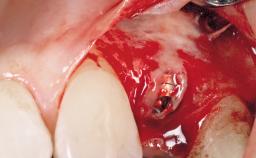

A 42-year-old female patient was referred to our clinic at the School of Dentistry of the University of São Paulo in November 2004, presenting a deficient restoration in the upper left central incisor. The clinical examination revealed no gingival retraction or any signs of gingival inflammation and, therefore, previous periodontal treatment was not considered. The patient presented a high lip line at full smile and a thin tissue biotype. This combination characterized a high-risk situation from an anatomic point of view, which required careful preoperative planning and cautious surgical execution.

Placement Protocol Immediate implant placement

Socket Morphology Single-root socket

Socket Integrity Sufficient, with intact bone walls

Bone Volume Sufficient, with intact walls